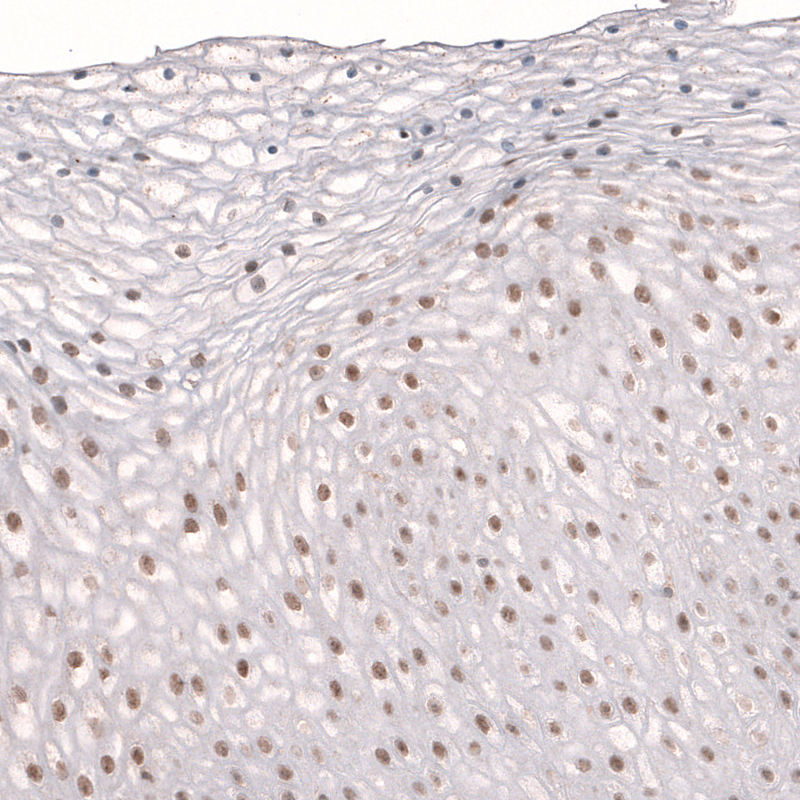

Immunohistochemical staining of human placenta shows moderate nuclear positivity in a subset of cells in chorionic villi.